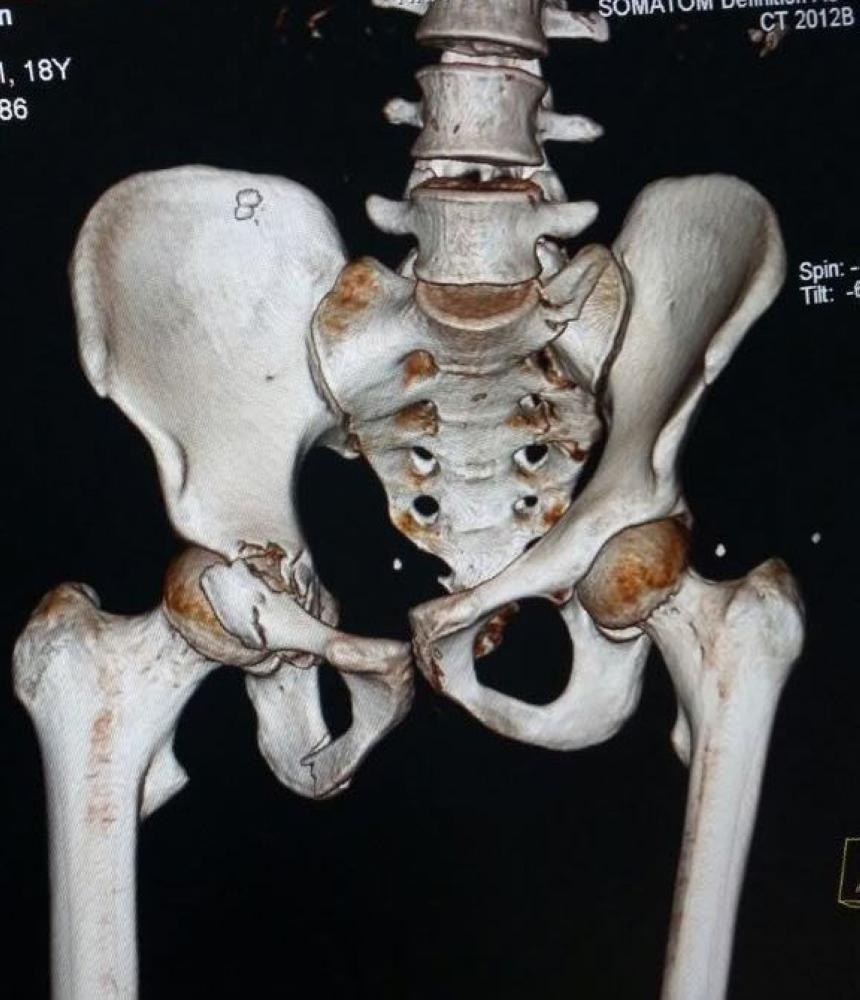

وقالت صحة الجوف إن المصاب تعرض لحادثة مرورية نتج عنها كسر بجسم الفقرة العنقية السادسة، وكدمات بالرئة اليمنى وكسر بالجدار الأمامي المكون لعظمة الحق «فنجان مفصل الفخذ»، وتوسع بعظام العانة وخلع خلفي بالمفصل الحرقفي الأيمن.